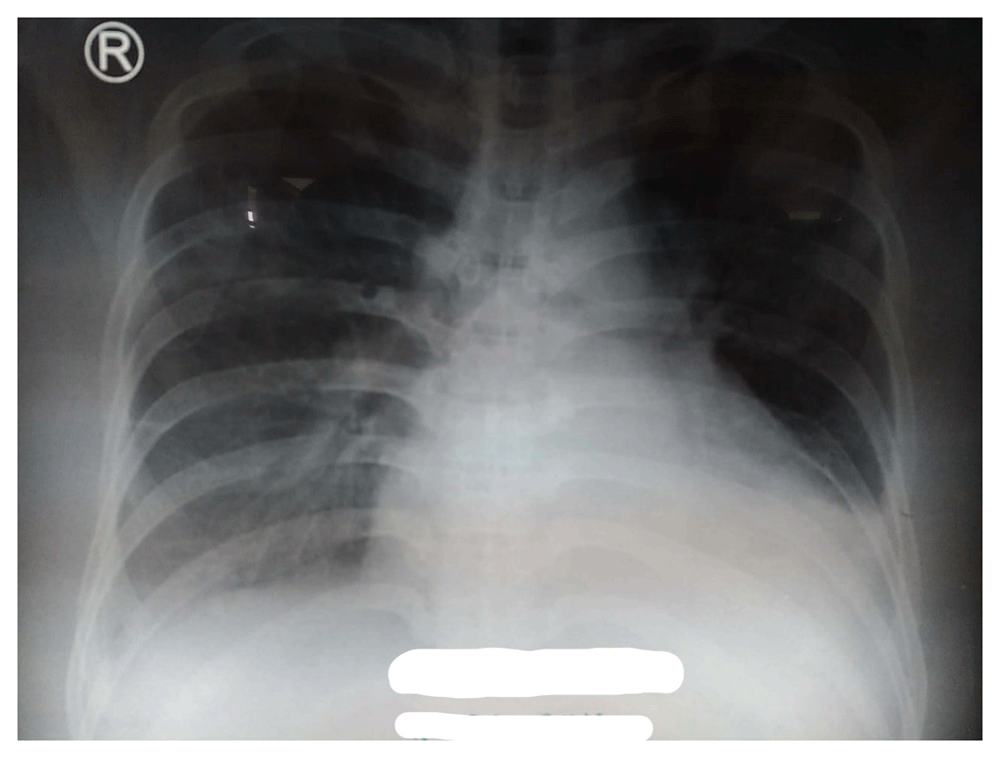

In laboratory findings, serum electrolytes revealed hypokalemia (K: 3.3 mmol/L; normal range 3.5–5.1 mmol/L), serum protein showed hypoalbuminemia (albumin: 3.1g/dL; normal range 3.4–5.0 g/dL), while other parameters were between normal limits. An electrocardiogram (ECG) showed sinus tachycardia rhythm 125 bpm, right-sided frontal axis, horizontal axis clockwise rotation, and slow progression of R waves at V1–V4 (Figure 1). A chest X-ray showed cardiomegaly, pulmonary congestion, and minimal bilateral pleural effusion (Figure 2). Echocardiographic examination revealed moderate mitral regurgitation (dilated mitral annulus), dilatation of all cardiac chambers (LVIDd 5.8 cm), visible thrombus in IVC to RA, decreased left and right ventricular systolic function (EF teich 35%, TAPSE 1.3 cm), and global hypokinetic of the left ventricle with eccentric LVH. The scans from a transthoracic echocardiogram (TTE) showing thrombus is shown in Figure 3 and Figure 4.